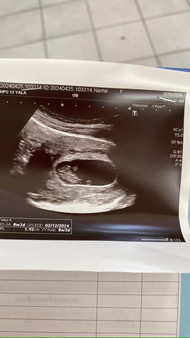

ซาวครั้งแรกตอน8วิค ปัจจุบัน 16วิคแล้วค่ะ ลูกคนแรก ตื่นเต้นสุดๆลุ้นเพศต่อ🥰🥰